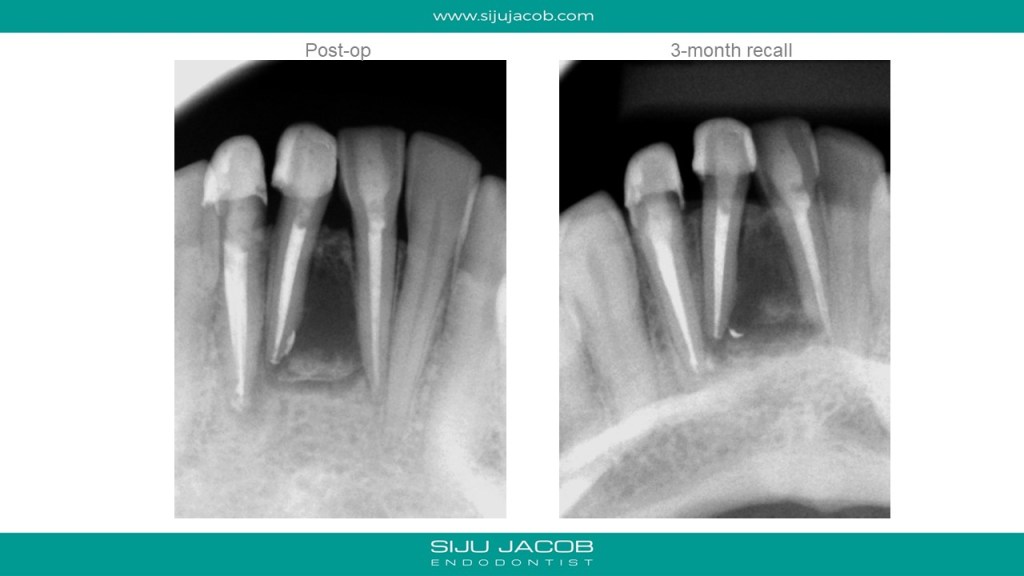

This case seemed to be responding well to conventional treatment. There wasn’t any drainage, so I obturated. The patient kept getting pain in the labial surface. So, we decided to do de-compression. The tooth reponded well to decompression and we saw very good healing at 6-months post de-compression. I saw this patient again 2 years later and someone meanwhile had gone and placed joint crowns on these teeth. Oh well….